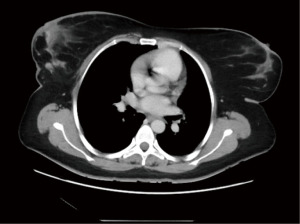

Retrospectively, we reviewed the patient’s mammogram, MRI and CT scan. All the images were consistent with a bilateral RS which is more obvious on the right side as the muscle fibers were longer and wider (Figures 2-4).

Retrospective review of her imaging revealed the presence of a unilateral RS muscle (Figures 6,7).